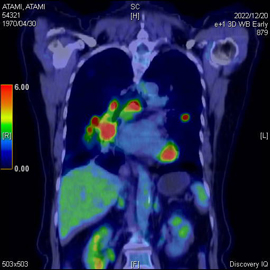

PET-CT検査とはPETとCTを同時に行える検査です。この検査の最大の利点はPET装置とCT装置を一体化することにより、PETの「機能画像」と、CTの「形態画像」を時間差や体位のズレなどがほぼない高精度な融合画像を作成できることです。癌の早期発見、転移・再発の有無、治療効果判定などに大変有効です。

当院のPET検査に使用される薬剤は18F-FDGといって、ブドウ糖に類似したFDGという物質に微量な放射線を出す放射性同位元素を結合させた薬剤です。がん細胞は正常な細胞より3~8倍多くのブドウ糖を取り込むという性質があり、それを利用してFDGの多く集まった部位を画像上で特定します。FDGはブドウ糖の類似体なので薬剤による副作用はほぼありません。

PET-CTの画像